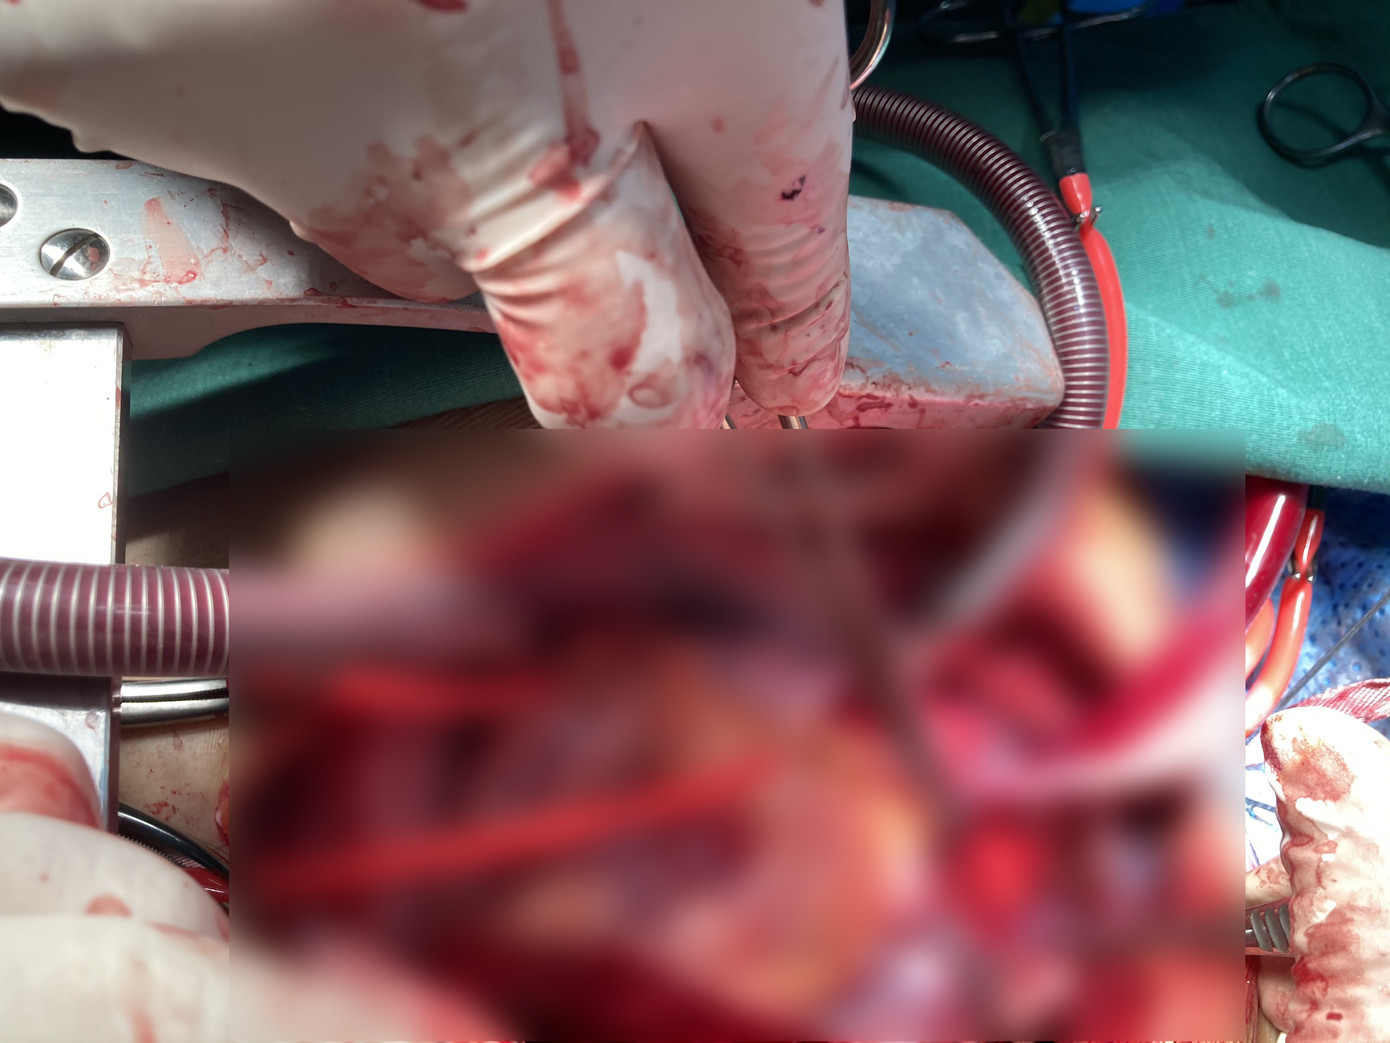

Cuộc đại phẫu đã được tiến hành khẩn cấp, với sự phối hợp giữa hai khoa Hồi sức – Phẫu thuật tim trẻ em và khoa Ngoại tổng quát. Để tái tạo lại eo động mạch chủ đã vỡ, các bác sĩ khoa Hồi sức – Phẫu thuật tim trẻ em đã phải trải qua cuộc đại phẫu kéo dài 10 giờ, sử dụng những kỹ thuật cao như hệ thống tuần hoàn ngoài cơ thể và kỹ thuật hạ thân nhiệt.

Sau đó, ê-kip thứ hai thuộc khoa Ngoại tổng quát mất thêm 4 tiếng để tiến hành mở bụng và xử trí những ổn thương bên trong bụng, gồm có thủng hỗng tràng và xước các thanh mạc ruột.

Cuộc đại phẫu kéo dài 14 tiếng do các bác sĩ Chợ Rẫy thực hiện.

Cuộc đại phẫu kéo dài 14 tiếng do các bác sĩ Chợ Rẫy thực hiện. TS.BS Lê Thành Khánh Vân, Trưởng khoa Hồi sức – Phẫu thuật tim trẻ em, Bệnh viện Chợ Rẫy cho biết, khi tiếp nhận bệnh nhân, các bác sĩ hết sức ngạc nhiên bởi bệnh nhân không bị chấn thương bên ngoài thành ngực, nhưng bên trong, nội lực của chấn thương rất lớn, xé rách eo động mạch chủ.

Trong đó, ê-kip của khoa Hồi sức – Phẫu thuật tim trẻ em đã phẫu thuật thay đoạn eo động mạch chủ đã vỡ bằng một động mạch nhân tạo, ê-kip khoa Ngoại tổng quát xử lý các tổn thương ở bụng. Sau cuộc đại phẫu, hiện tại tình trạng bệnh nhân đã ổn định và dự kiến sẽ được xuất viện vào cuối tuần này.